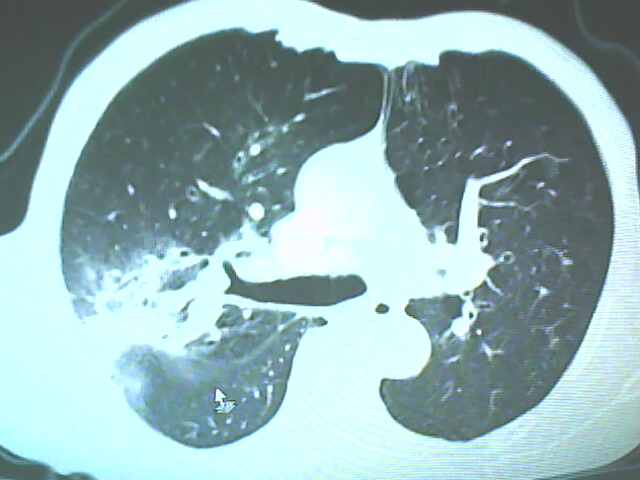

考虑癌性空洞可能性大,空洞内壁不规则,病灶周围模糊,分叶、有毛刺

考虑癌性空洞可能性大,空洞内壁不规则,病灶周围模糊,分叶、有毛刺。

空洞内壁不规则,病灶周围模糊,分叶、毛刺呈日光放射状,突然截断,支持考虑癌性空洞

考虑癌性空洞可能性大,内壁不规则,洞壁薄厚不均呈结节状突起,边缘模糊,分叶,毛刺

典型癌性空洞(偏心性,壁厚薄不均,内壁不光整),周围毛刺较僵硬,且有刺突征和血管聚集征